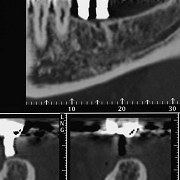

CT撮影による診査・診断

インプラント手術では 顎の骨にインプラントを植えます。

顎の骨の形や 血管・神経の位置、隣の歯の根の位置は 人それぞれで 普通のレントゲン撮影では はっきりとは見ることができません。

当院では CT撮影をすることにより これらの位置を把握し 的確なインプラントの位置や大きさを診査・診断し 安全に手術を行います。

ハートフルにわの歯科医院 インプラントCT撮影